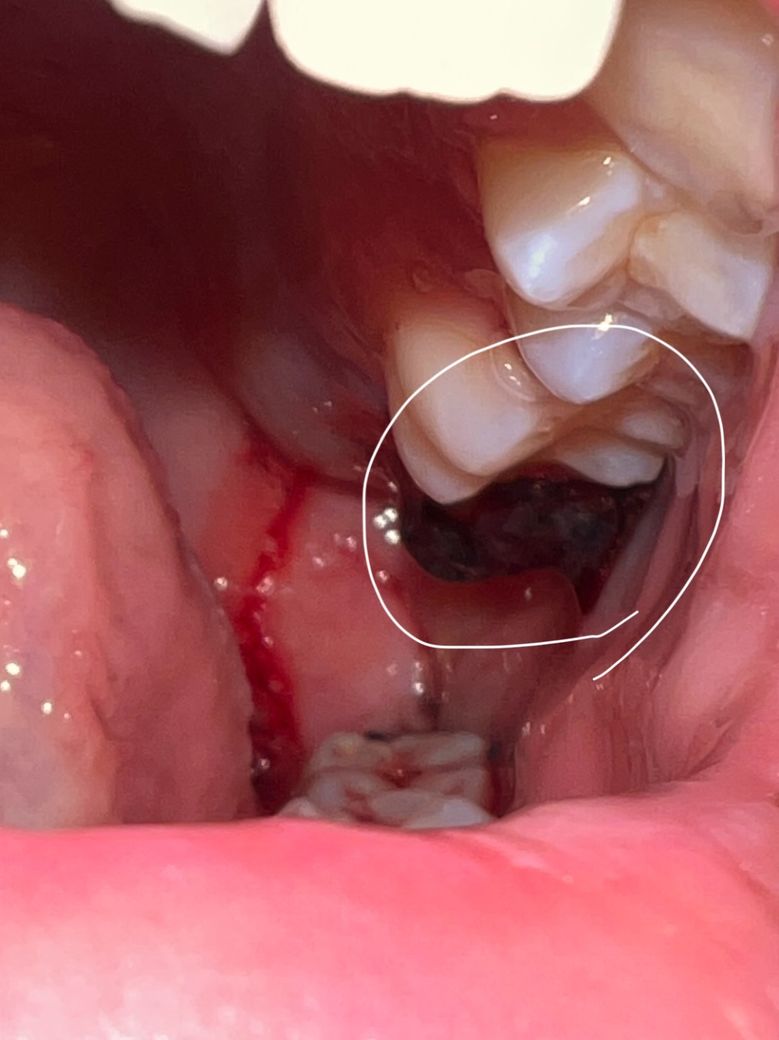

사랑니를 뽑았는데 위에 이게 혈병인건가요?

위에 자꾸 뭉툭한게 느껴져서 조금 불편한데 이게 혈병인건가요? ㅜㅜ 아니라면 대체 뭘까요… 원래 사랑니를 빼면 저렇게 되는게 맞는 건가요?

위에 자꾸 뭉툭한게 느껴져서 조금 불편한데 이게 혈병인건가요? -> 네 피떡입니다 굳이 제거하려고 하지 마세요

사랑니를 발치하고 나면 발치한 부위에 사진처럼 혈병이 형성될수 있습니다. 크게 문제가 되지는 않으며 혈병이 제거되지 않도록 주의를 하는것이 좋습니다.

혈병이 제거되게 되면 발치한 부위가 출혈이 되어 치유가 늦어 질수 있습니다.

사랑니 뽑은 후 혈병이 발치한 자리 위로 나온 것입니다. 그냥두면 저절로 떨어집니다. 그러나 입을 다물면 눌러지거나 피가 나면 치과로 가서 치료 받아야 합니다.

아직 지혈이 제대로 된거 같지 않으니 거즈를 더 꽉 깨물고 계시는게 좋을것같습니다. 혈병은 쉽게 말해서 피가 굳으면서 생기는걸 말합니다.